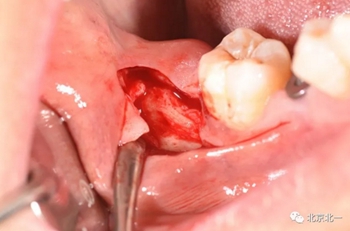

第二步:拔牙

切口設(shè)計(jì)關(guān)鍵點(diǎn)偏頰側(cè)。